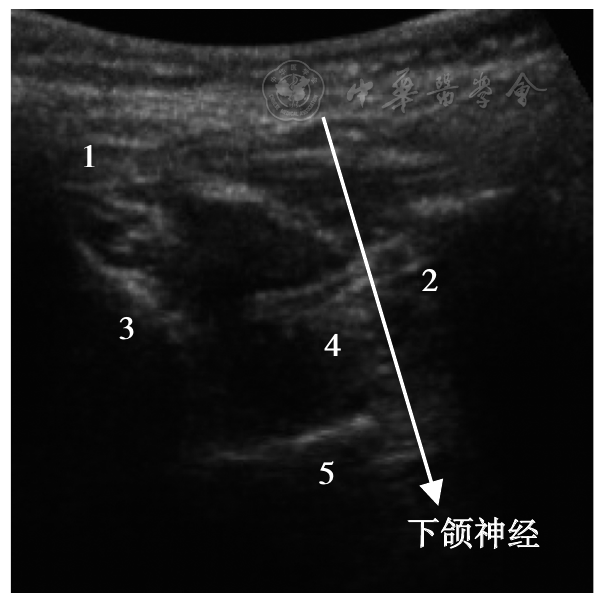

图2 超声引导下颌神经DNB示意图1为冠突,2为髁突,3为上颌骨,4为翼外肌,5为蝶骨翼突外侧板;DNB:诊断性神经阻滞

Fig.2 Ultrasound-guided mandibular nerve DNB schematic diagram